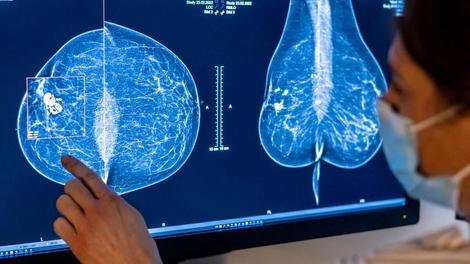

تشخیص بی نقص سرطان سینه با هوش مصنوعی

مطالعات اخیر نشان داده اند که تصویربرداری از سینه به کمک هوش مصنوعی (AI) پتانسیل کاهش تعداد قابل توجهی از آن دسته سرطان‌های سینه‌ای را دارد که طی روند غربالگری معمول ماموگرافی تشخیص داده نمی‌شوند.

بر اساس پژوهشی که از طریق سری مجلات ناشر بین المللی اشپرینگر ساینس+بیزینس مدیا قابل دسترسی است، یک گزارش اولیه در مورد ماموگرافی به کمک هوش مصنوعی نشان داد که ۳۱ درصد از سرطان‌هایی که در ماموگرافی استاندارد تشخیص داده نمی‌شوند، از طریق هوش مصنوعی قابل شناسایی اند.

همچنین با استناد به گزارشی جدیدتر از بخش سلامت شبکه خبری آمریکایی سی ان ان، دانشمندان به کشفی بزرگ دست یافته اند؛ تشخیص سرطان پستان به کمک هوش مصنوعی ۴ سال قبل از اینکه بتوان آن را به وسیله ماموگرافی استاندارد تشخیص داد! این مطالعات به وضوح نشان می‌دهند که ماموگرافی با کمک هوش مصنوعی می‌تواند سرطان سینه را بسیار سریعتر از روش‌های تشخیصی متداول ردیابی و با تشخیص زودهنگام آن را تبدیل به گزینه‌ای قابل درمان کند.